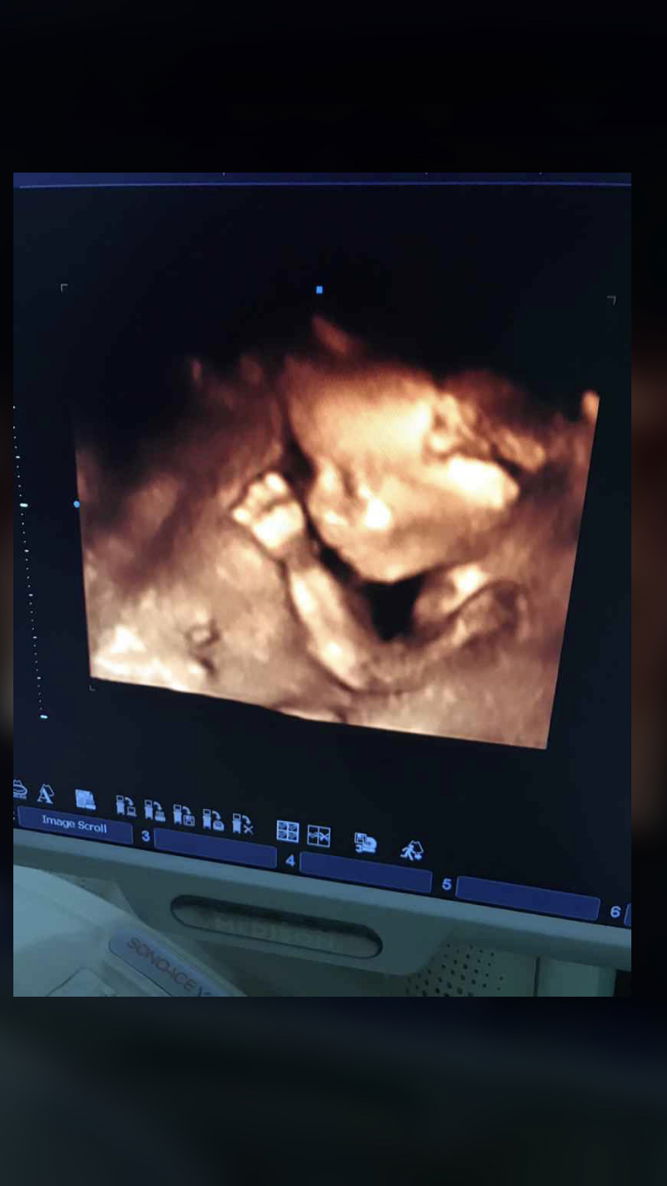

USG

Bun itu usg 2D atau 4D yaa ?? Yang bisa bener2 fokus & jelas terlihat janin kita.